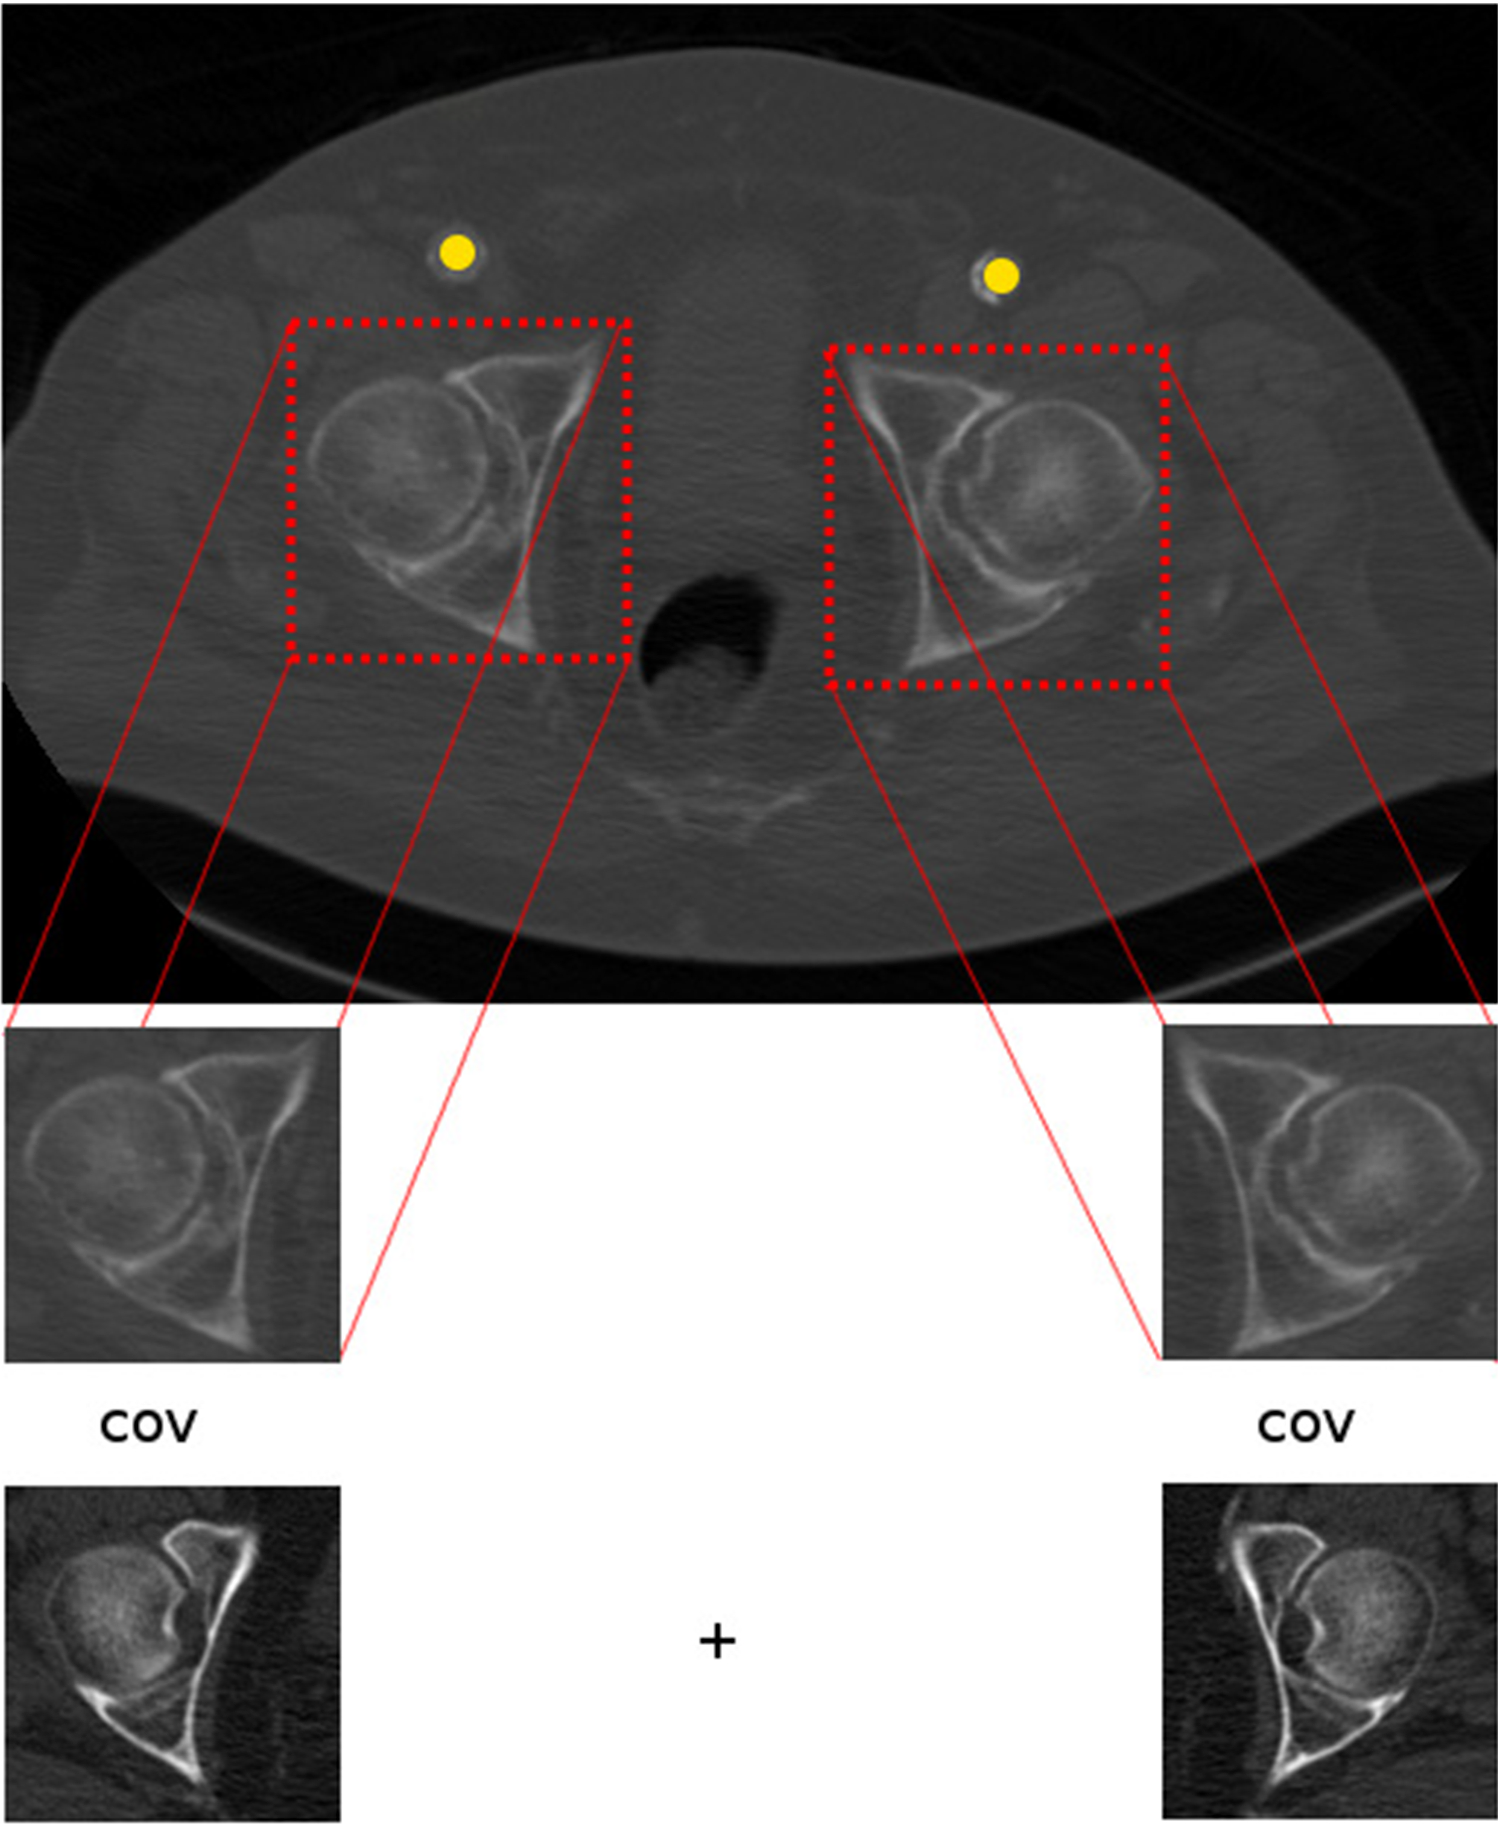

Fig. 4

This figure visualizes how the template matching detects the caput femoris in the CT slice

As the HU values in CTA volumes can show a high degree of variability in the artery a normalized cross-correlation measure was implemented as similarity function between the template and the image patches of the considered axial slice extracted in a sliding-window manner. The slice that resulted in the highest value of the similarity function was determined as the SOI regardless of the number of used templates or in case of SOI 3 the number of sets of templates. To measure the similarity for the determination of SOI 3 a set of templates was defined and their mean of their individually obtained cross-correlation values was computed (Fig. 4).

Because of the lower diameter of the arteria femoralis communis after applying the vesselness filter to the SOI 3 a thresholding is applied to exclude bone material and calcification. The algorithm returns ROI 1, 2 and 3 as input for the concluding assessment.